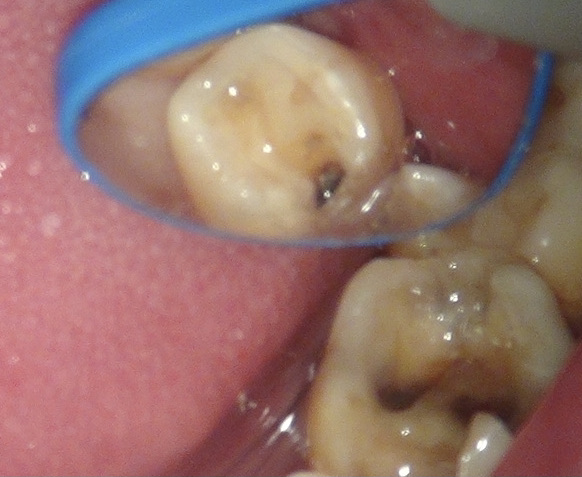

お口の中を見ると。

レントゲンの赤丸の部分がむし歯。